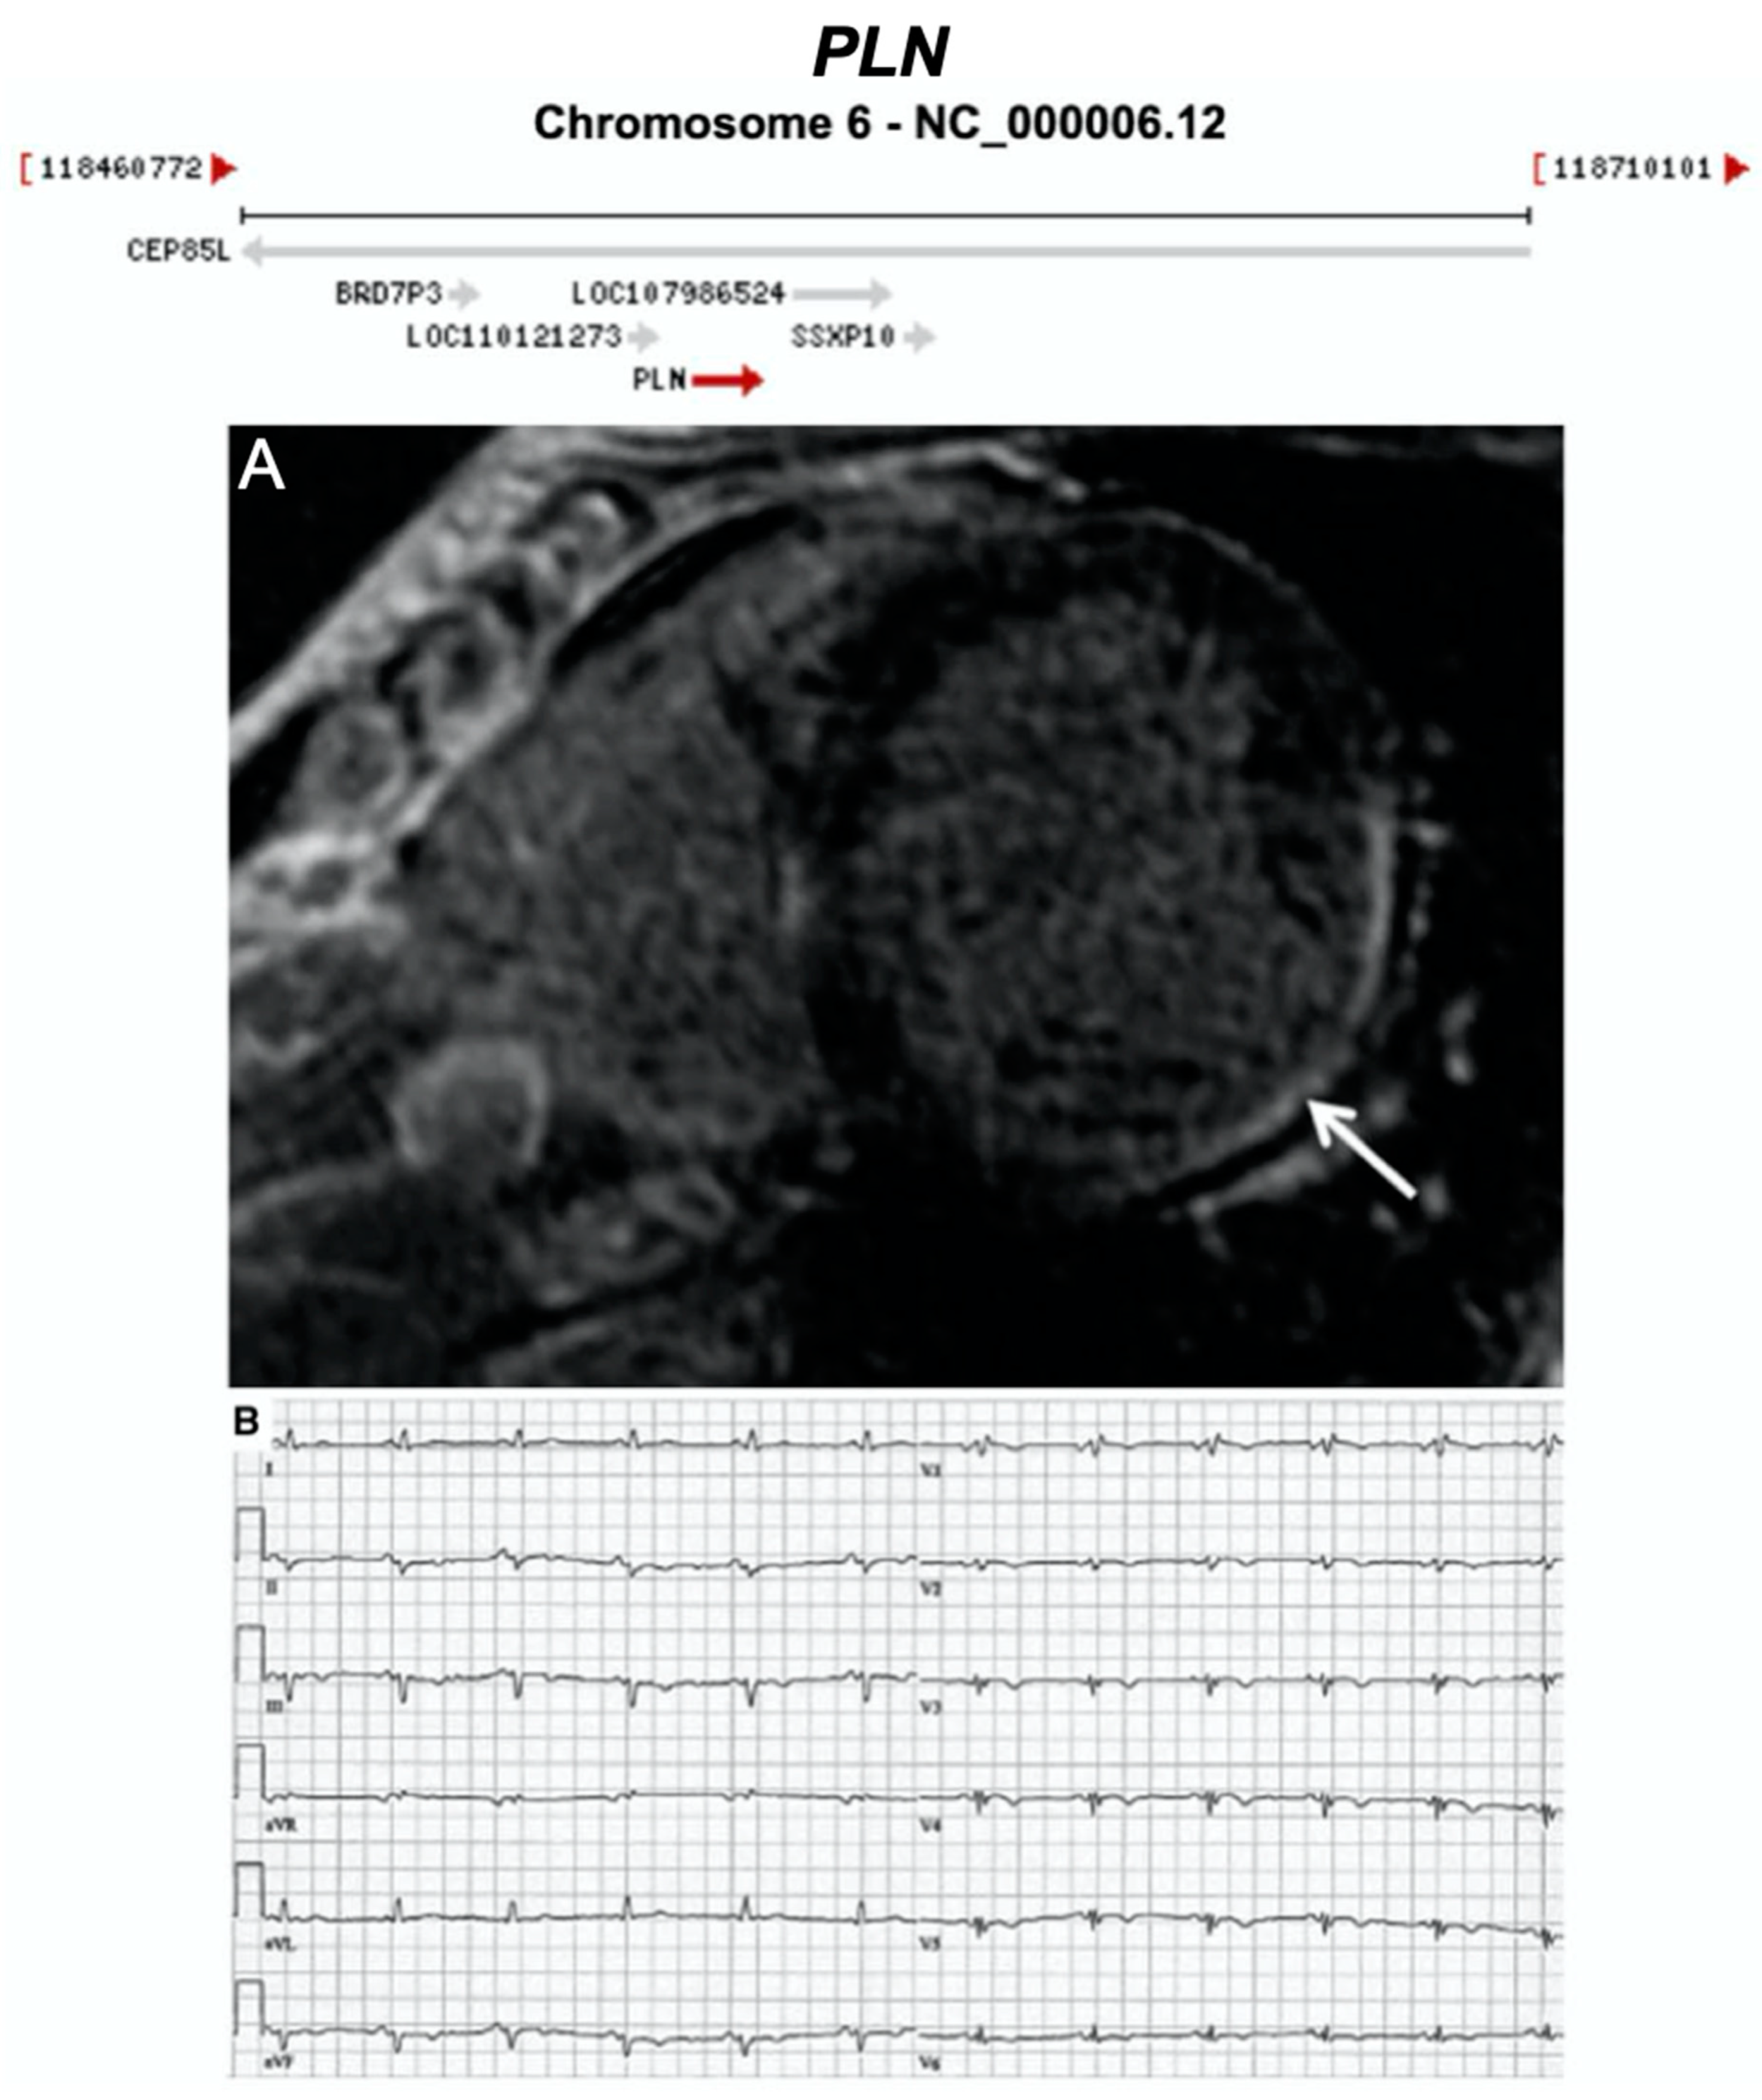

Figure 16.

Exemplar MRI and ECG finding found in ACM patients with PLN mutations. (A) CMR image from a patient with PLN p.Arg14del mutation showing inferolateral wall thinning and late-gadolinium enhancement of the LV inferolateral wall; (B) 12-lead ECG of the same patient showing normal sinus rhythm with low voltages in all leads (<0.5 mV) and flattened or inverted T-waves in V1-V6 and inferior leads (II, III, aVF). Reproduced with permission from te Rijdt et al. (2019) [47].